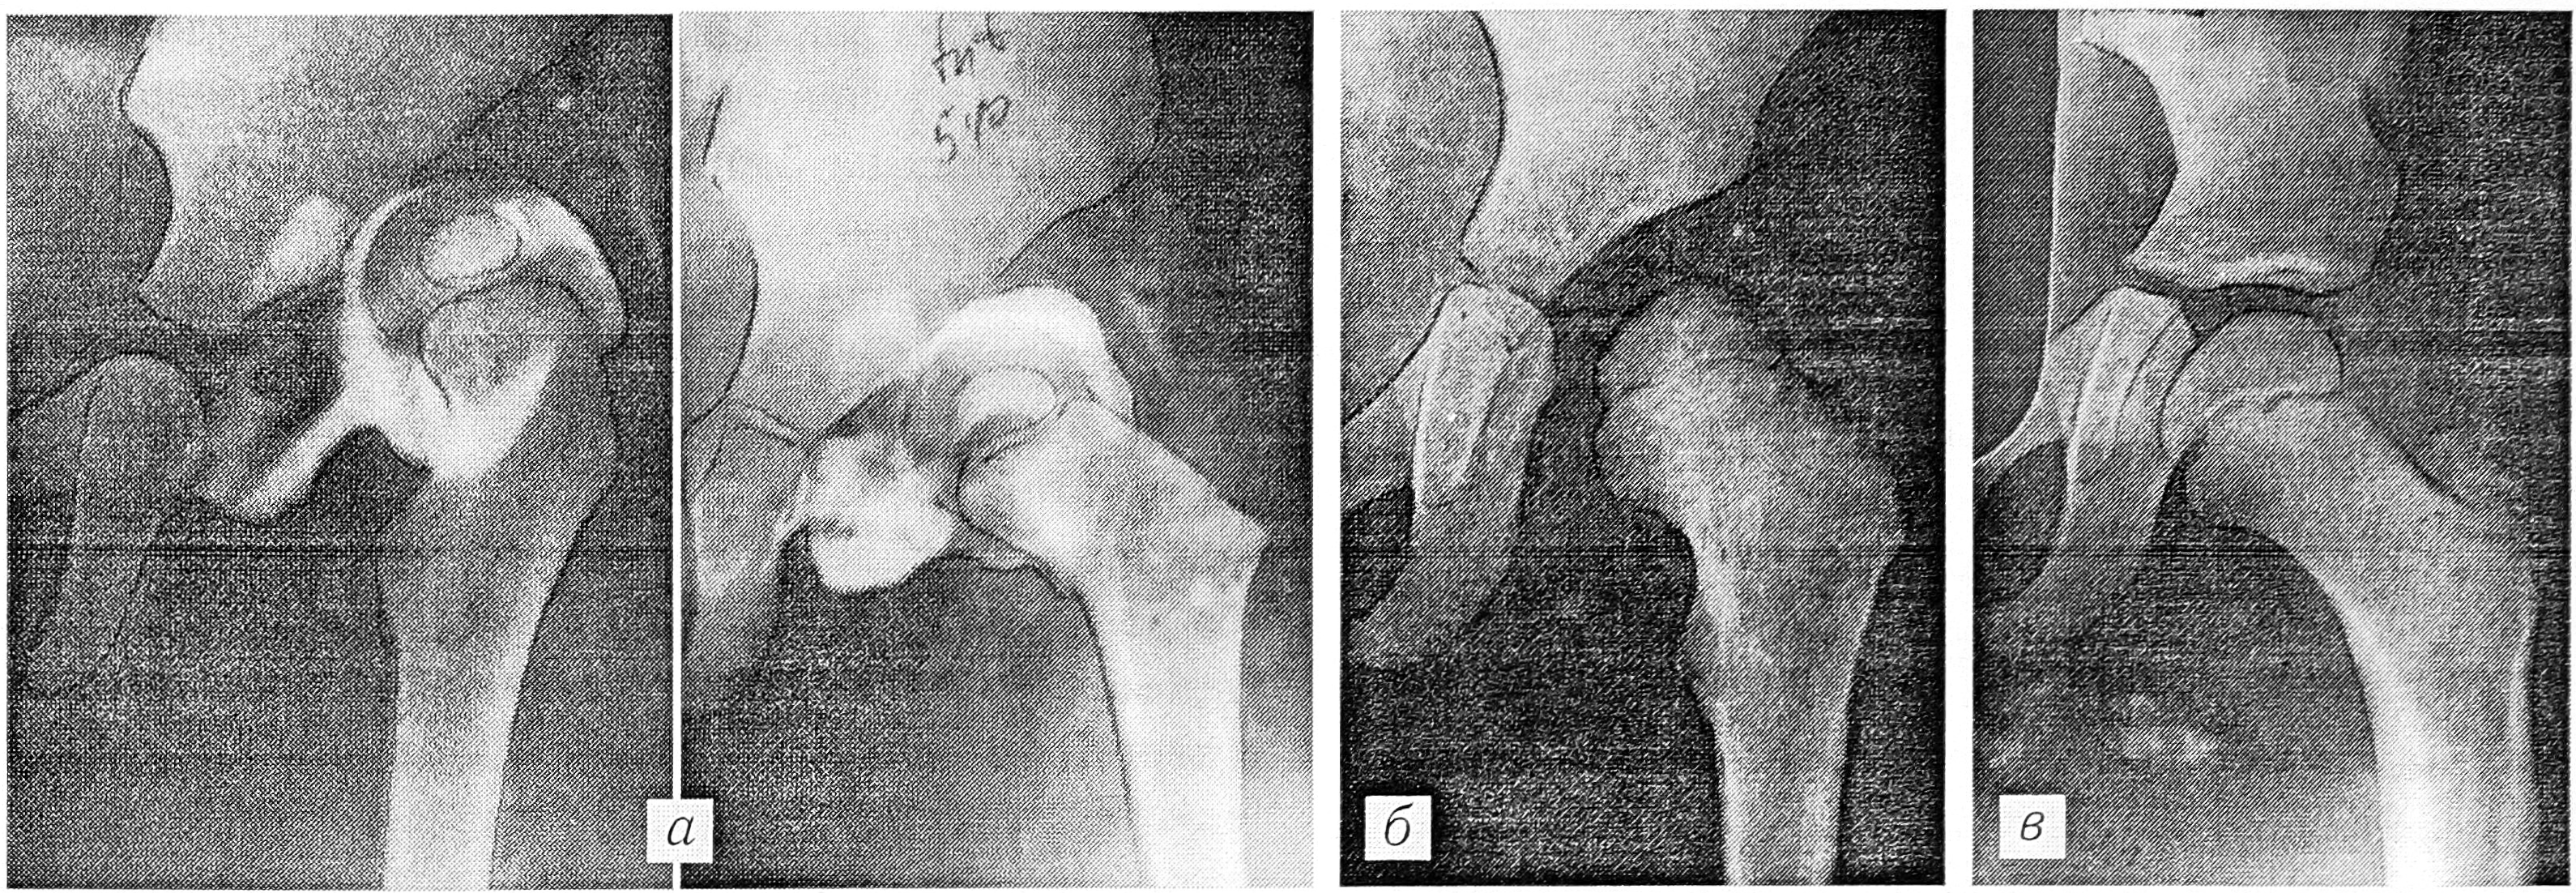

— размеры головки и впадины, по данным артрографии, соответствуют друг другу или сопоставимы. Перешеек капсулы и вход во впадину существенно расширяются при внутренней ротации бедра (рис. 1).

Рис. 1. Больная К. 1 года 10 мес: а — артрограммы в двух проекциях: контрастное вещество распространяется с внутренней стороны от лимбуса, при внутренней ротации вход во впадину увеличивается, лимбус изменяет положение; б — через 1,5 года после закрытого вправления; в — через 1,5 года после деторсионно-варизирующей остеотомии бедренной кости и остеотомии таза по Солтеру.